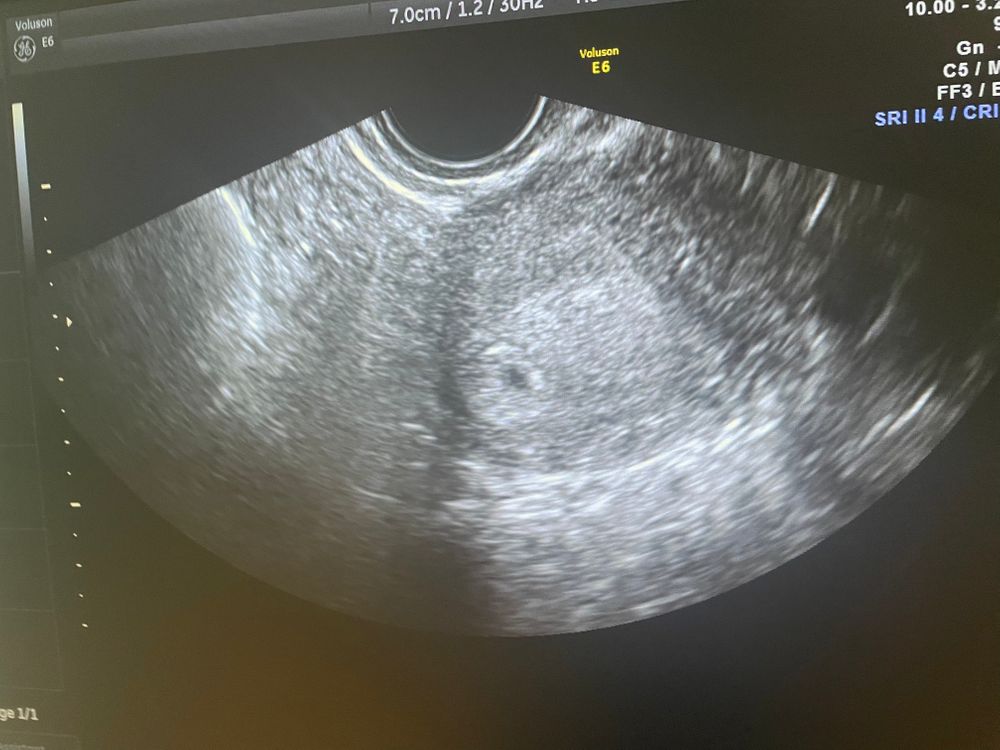

Узи на 22 ДПО❤️

знаю, что очень рано я пошла на узи, но это первая беременность, хочется знать что все в порядке, хотела исключить внематочную беременность.

Плодное яйцо 5.2 мм, врач была немногословной, толком ничего не сказала.

5,2 мм соответствует сроку 5 недель и 2 дня или 23 ДПО.

Все у вас отлично.